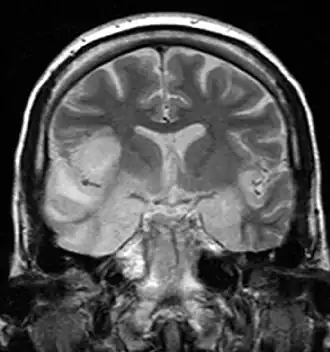

Symptomen als misselijkheid, braken, beven, nekstijfheid, koorts, zware hoofdpijn, maar ook verlamming en epileptische aanvallen komen voor. Om een goede diagnose te stellen zal er bloedonderzoek en een ruggenprik gedaan moeten worden. Vaak zal er ook een MRI- of CT-scan gedaan worden. Onbehandeld kan encefalitis binnen enkele uren leiden tot de dood.